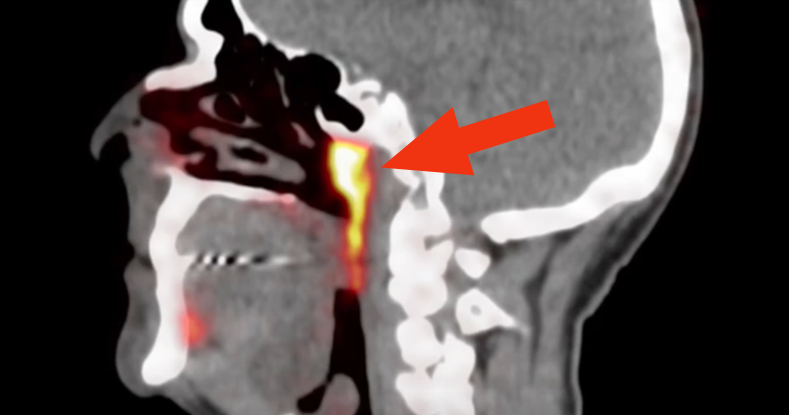

„Непознатиот објект“ бил идентификуван случајно од страна на лекари во Холандија кои испитувале пациенти со рак на простата со напреден скен наречен PSMA PET/CT. Кога ќе се спои со одредени инјекции, оваа алатка за дијагноза ги нагласува туморите во телото. Сепак, во овој случај покажала нешто сосема друго, сместено зад назофаринксот.

Новото откритие на тимот на Вогел е многу поголемо и покажува нешто што изгледа дека е претходно занемарен пар жлезди - наводно четвртиот сет на поголеми плунковни жлезди - лоциран зад носот и над горното непце, во близина на центарот на главата.

- Излезе дека двете нови области имаат и други карактеристики на плунковни жлезди. Ние ги нарекуваме тубаријални жлезди, што се однесува на нивната анатомска локација (над Torus tubarius) - истакнува првиот автор на студијата, оралниот хирург Матијс Валстар од Универзитетот во Амстердам.

Во однос на тоа како е можно овие жлезди претходно да не биле забележани, истражувачите посочуваат дека структурите се најдени на тешко достапна анатомска локација, под основата на черепот. Можно е отворите на каналите да биле забележани, велат истражувачите, но можеби не биле забележани како тоа што се. Дополнително, само поновите техники би можеле да ја детектираат структурата како плунковна жлезда.